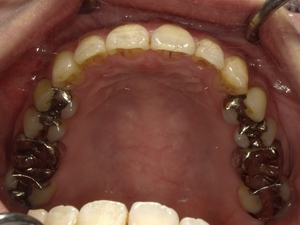

Before After

●ご相談内容:前歯が曲がっている●矯正の種類:マウスピース型「矯正インビザラインGO」●治療期間:18週●治療費用:66万円(税込)